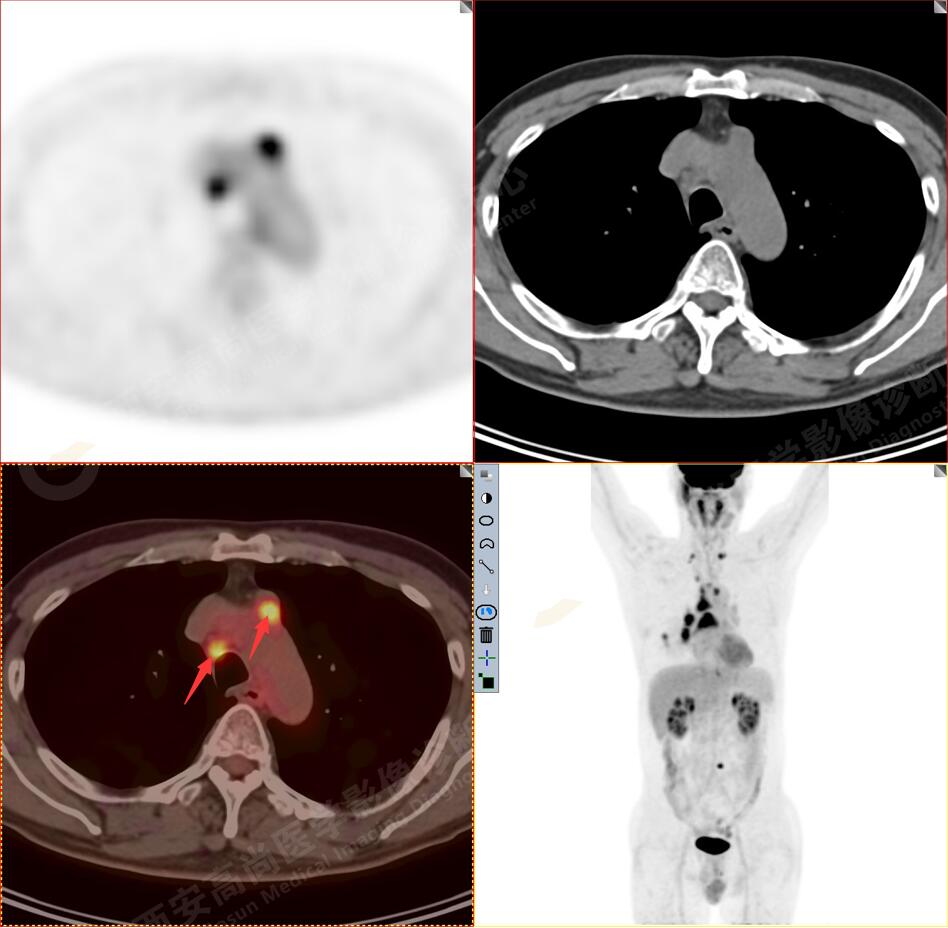

2.以下為全身多發(fā)轉移灶

3.右側肺門、縱隔(1L、1R、3A、4、6、7組)及雙側鎖骨上多發(fā)腫大淋巴結,呈不同程度FDG代謝異常增高,考慮為淋巴結轉移。